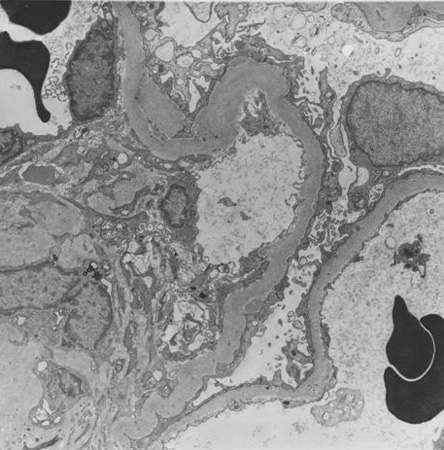

Diabetic kidney disease

Diabetic kidney disease: mesangial expansion is usually recognised when it has exceeded 1.5 times the normal mesangial matrix

From the collection of Dr Raoul Fresco; used with permission